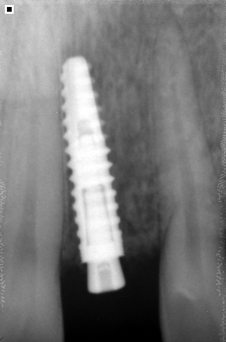

El proceso de utilizar implantes inicia con un completo examen clínico y por imágenes de nuestros pacientes para determinar el estado de salud bucal y dental (dientes, encías, hueso alveolar, etc.) y salud en general con el fin de obtener un diagnóstico y plan de tratamiento seguro, cómodo y duradero.

Reemplazamos la pieza dental original por una fabricada en Titanio biocompatible que se introduce en el hueso de la mandíbula, sobre ésta nueva raíz se fija una pieza de metal y cerámica (corona) resistente que se iguala en color y forma con el fin de brindar un aspecto lo más natural posible.

- El implante se fusiona con el hueso mandibular, proporcionando un soporte estable para los dientes artificiales